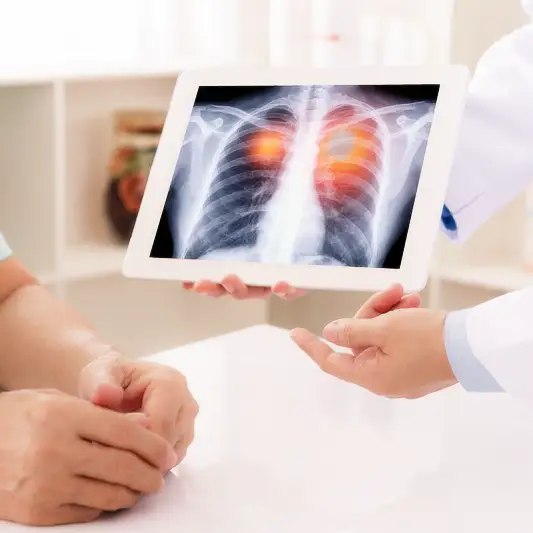

폐암 1기 진단을 위해서는 정기적인 검진이 중요합니다. 폐암 검진에는 흉부 X-선, CT 스캔, PET 스캔 등이 사용될 수 있습니다. 이러한 검사를 통해 의사는 폐암의 존재 여부와 정확한 위치를 확인할 수 있습니다. 또한 폐암의 크기, 종류, 세포의 특성 등을 파악하여 적절한 치료 방법을 결정할 수 있습니다.

폐암 1기 진단은 환자에게 많은 이점을 제공합니다. 첫째로, 조기에 발견되면 폐암의 치료 가능성이 크게 향상됩니다. 크기가 작고 퍼진 부위가 적은 폐암은 수술이나 방사선 치료 등을 통해 완전히 제거할 수 있는 경우가 많습니다. 둘째로, 폐암이 진행되기 전에 발견되면 생존율이 상당히 높아집니다. 폐암은 조기에는 증상이 나타나지 않거나 미미하기 때문에 적극적인 검진이 필요합니다.